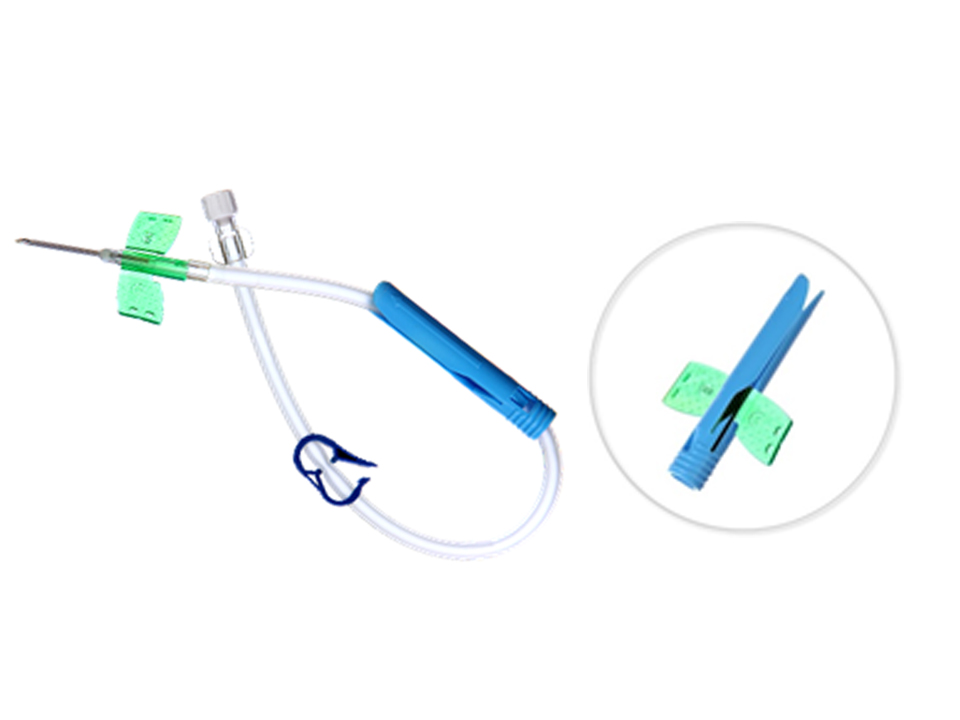

Nouvo Safety Set

Our new generation Closed IV Catheter system has resulted in an improvement in both patient care and protection of the professionals in the healthcare domain. There is an integrated system that minimizes the number of manipulations.

- Micro Clave** Clear Connector Reduces The Risk Of Catheter-Related Bloodstream Infections (CRBSI)

- User Friendly, Self Activating Safety Mechanism Prevents Needle Stick Injuries.

- Flexible Perforated Soft Wings

- Quick Flashback Needle Technology ensures successful venipuncture.